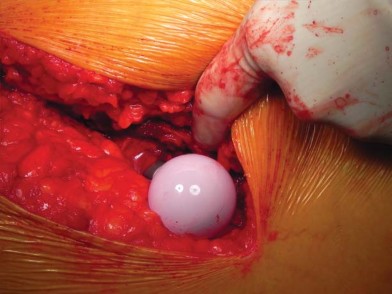

تحضير الفخذ والحق

يتم تحديد مستوى قطع عنق الفخذ مسبقًا بالتخطيط (باستخدام الأشعة السينية) ومواءمته أثناء الجراحة مع المدور الكبير. بعد قطع عنق الفخذ، يتم تحضير الحُق بالطريقة القياسية قبل تحضير الفخذ. يفضل الأستاذ الدكتور محمد هطيف عادةً وضع الكأس وفقًا للمعالم التشريحية لإعادة إنشاء التوجيه الطبيعي للحُق لدى المريض ويتحقق من الإصدار والميل الصحيحين عن طريق الجس والرؤية المباش